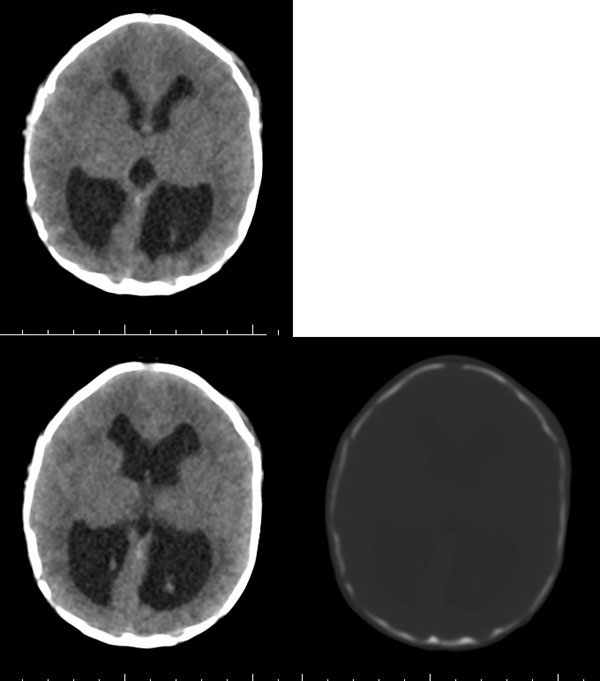

2天,枕部肿物

枕骨缺损,脑膜脑膨出。同时第4脑室挤压变形、闭塞,致使第3脑室、双侧侧脑室显著积水、扩张,过高的颅内压推挤脑实质,致使颅骨内板出现多而且深的脑回样压迹,脑细胞水肿,皮质、白质分界不清。

考虑先天性中脑水管梗阻,其以上脑室扩大。枕部脑膜脑膨出!

枕骨脑裂畸形伴脑膜脑膨出,双侧脑室扩张积水,第四脑室变窄致使双侧侧脑室及第三脑室积水,

枕骨缺损,脑膜脑膨出。同时第4脑室挤压变形、闭塞,致使第3脑室、双侧侧脑室显著积水、扩张.

脑积水——第4脑室挤压变形、闭塞,致使第3脑室、双侧侧脑室显著积水、扩张

颅骨内面凹陷——过高的颅内压推挤脑实质,过高的颅内压推挤脑实质,致使颅骨内板出现多而且深的脑回样压迹